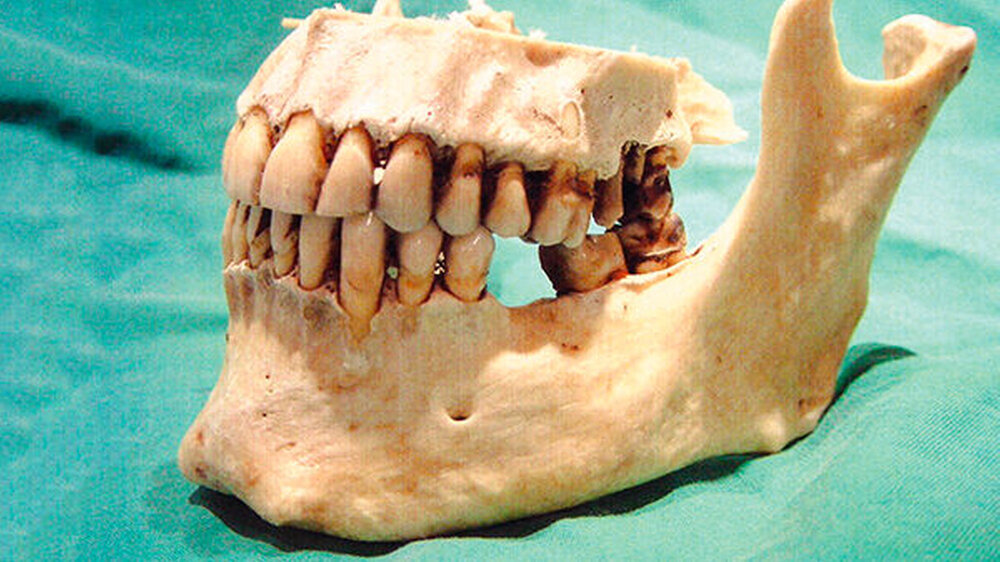

Am 14. März 2003 wurde in der Waal, bei der Gemeine Tiel (Niederlande) ein toter Mann gefunden. Er scheint aus Deutschland zu kommen. Allem Anschein nach lag die Leiche zwischen zwei bis vier Wochen im Wasser.

Das Alter des Toten wird zwischen 30 und 50 Jahren geschätzt. Er hatte schwarze Haare und trug einen Schnurrbart. Seine Größe betrug etwa 175 Zentimeter. Er trug blaue Adidas Sportschuhe in Größe 42, eine blaue Jeans der Marke EDWIN, Größe W31-L32 und dazu einen schwarzen Pullover mit Rollkragen. An seinem rechten kleinen Finger hatte er einen goldenen Trauring. Der Mann war beschnitten.